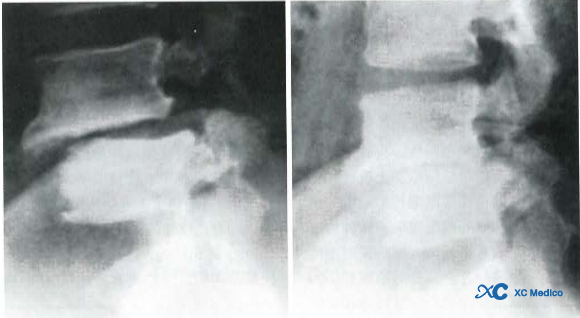

Примечание: инфекция Brucella Lumborum, рентгенограммы показывают склероз поясничных позвонков, переднее проскальзывание поясничных позвонков, нерегулярное пошаговое разрушение на переднем крае тела позвоночного и образование костных крибрариформ на переднем крае тела позвоночного.